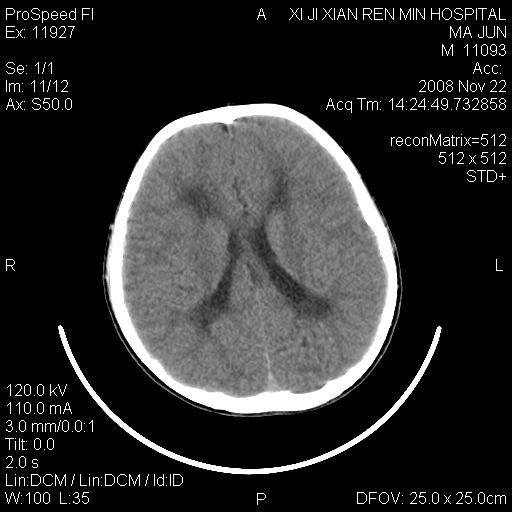

标题: PED1650:男 8岁 间断抽搐2年 两岁是在外院诊断脑瘫 当时CT示 [打印本页]

标题: PED1650:男 8岁 间断抽搐2年 两岁是在外院诊断脑瘫 当时CT示

双侧侧脑室前角,三角区旁及半卵圆中心区白质呈低密度改变,半卵圆中心区病灶呈片状融合趋势,无软化征像,脑室无扩张,各神经核团无异常改变,脑皮质无萎缩等征像,结合病史考虑髓鞘发育不良性脑白质病,异染性脑白质营养不良可能性大.不除外多发性硬化等其他改变,建议磁共振检查

脑白质减少,双侧侧脑室额角旁及半卵圆中心可见对称性略低密度影,边缘尚清,考虑脑白质发育不良